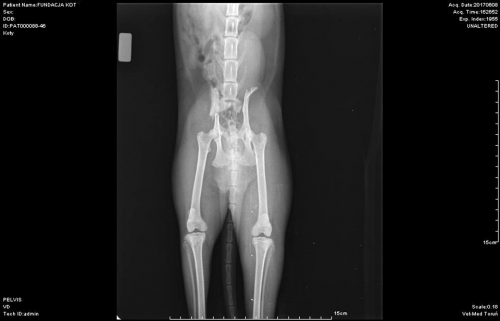

Rtg

Rtg kici